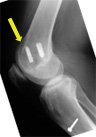

Take a look at the femur (top bone). The white bits are the fixation devices holding the graft in the tunnel. The right X-ray shows the original tunnel (yellow arrow) with the new tunnel behind it and in the correct position. You get an idea of how far anterior the original tunnel was made. If you cannot orientate, look for the patella bone - that is the anterior aspect.